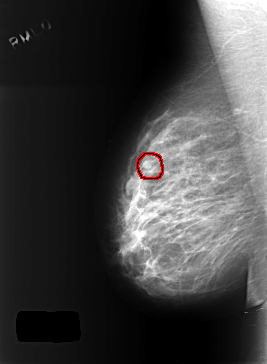

C_0402_1.RIGHT_MLO

FILE: C_0402_1.RIGHT_MLO.OVERLAY

TOTAL_ABNORMALITIES 1

ABNORMALITY 1

LESION_TYPE MASS SHAPE OVAL MARGINS CIRCUMSCRIBED

ASSESSMENT 3

SUBTLETY 4

PATHOLOGY BENIGN

TOTAL_OUTLINES 1

BOUNDARY